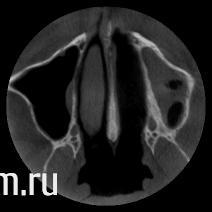

Dr.Politov Опубликовано 24 марта, 2012 Поделиться Опубликовано 24 марта, 2012 Здравствуйте уважаемые коллеги. Очень рад был наткнуться на этот сайт, в частности на форум. Немного о себе: Сам с провинциального города, врач челюстно-лицевой хирург. Пока в начале своего профессионального пути.Выкладываю ОПТГ на первичной консультации (27.12.11г.) и срезы КТ после санации (снятие конструкций, терапевт, пародонтолог) (22.03.12г.). Все удаления выполнялись в середине января. Сейчас этап решения что куда и в какой последовательности. У меня есть план, им я поделюсь ниже, но очень хочется послушать вас, чтобы укрепиться в своём плане или пересмотреть его. Верхняя челюсть:Бюгель, либо двойной синуслифт (после санации левого синуса), через 8 месяцев имплантаты, под несъёмную конструкцию или условно-съёмную.Надеюсь на бюгель согласится ))) Нижняя челюсть:4.5 - 3,75х104.6 - 3,75х104.7 - 4,2х103.4 - 3,75х103.6 - 5.0х10 (но тут вопрос, после удаления прошло 2,5 месяца... ждать или выполнить всё внизу одномоментно и прикрыться Bio-Oss + Bio-Gide? Либо мост на 3.5-3.7 зубы, так как они и так будут покрываться м/к). ps: Он активный курильщик (ещё поэтому я за бюгель на верху) Спасибо, как минимум за внимание ))) Ссылка на комментарий

Crossovok Опубликовано 24 марта, 2012 Поделиться Опубликовано 24 марта, 2012 Никаких бюгелей! Обсудите с ней возможность бросить курить на некоторое время, ознакомьте ее со статистикой осложнений для курильщиков (80% осложнений из 100% встречается у курильщиков). На ВЧ двухсторонний синуслифт, имплантация через 8 месяцев, нагрузка еще через 6-8 мес. На НЧ сложно судить, не зная размеров костного приложения. PS Бюгель - вред! Ссылка на комментарий